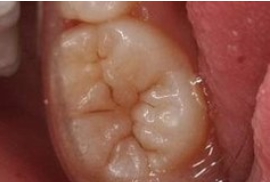

臼齒的保鏢─溝隙封填劑